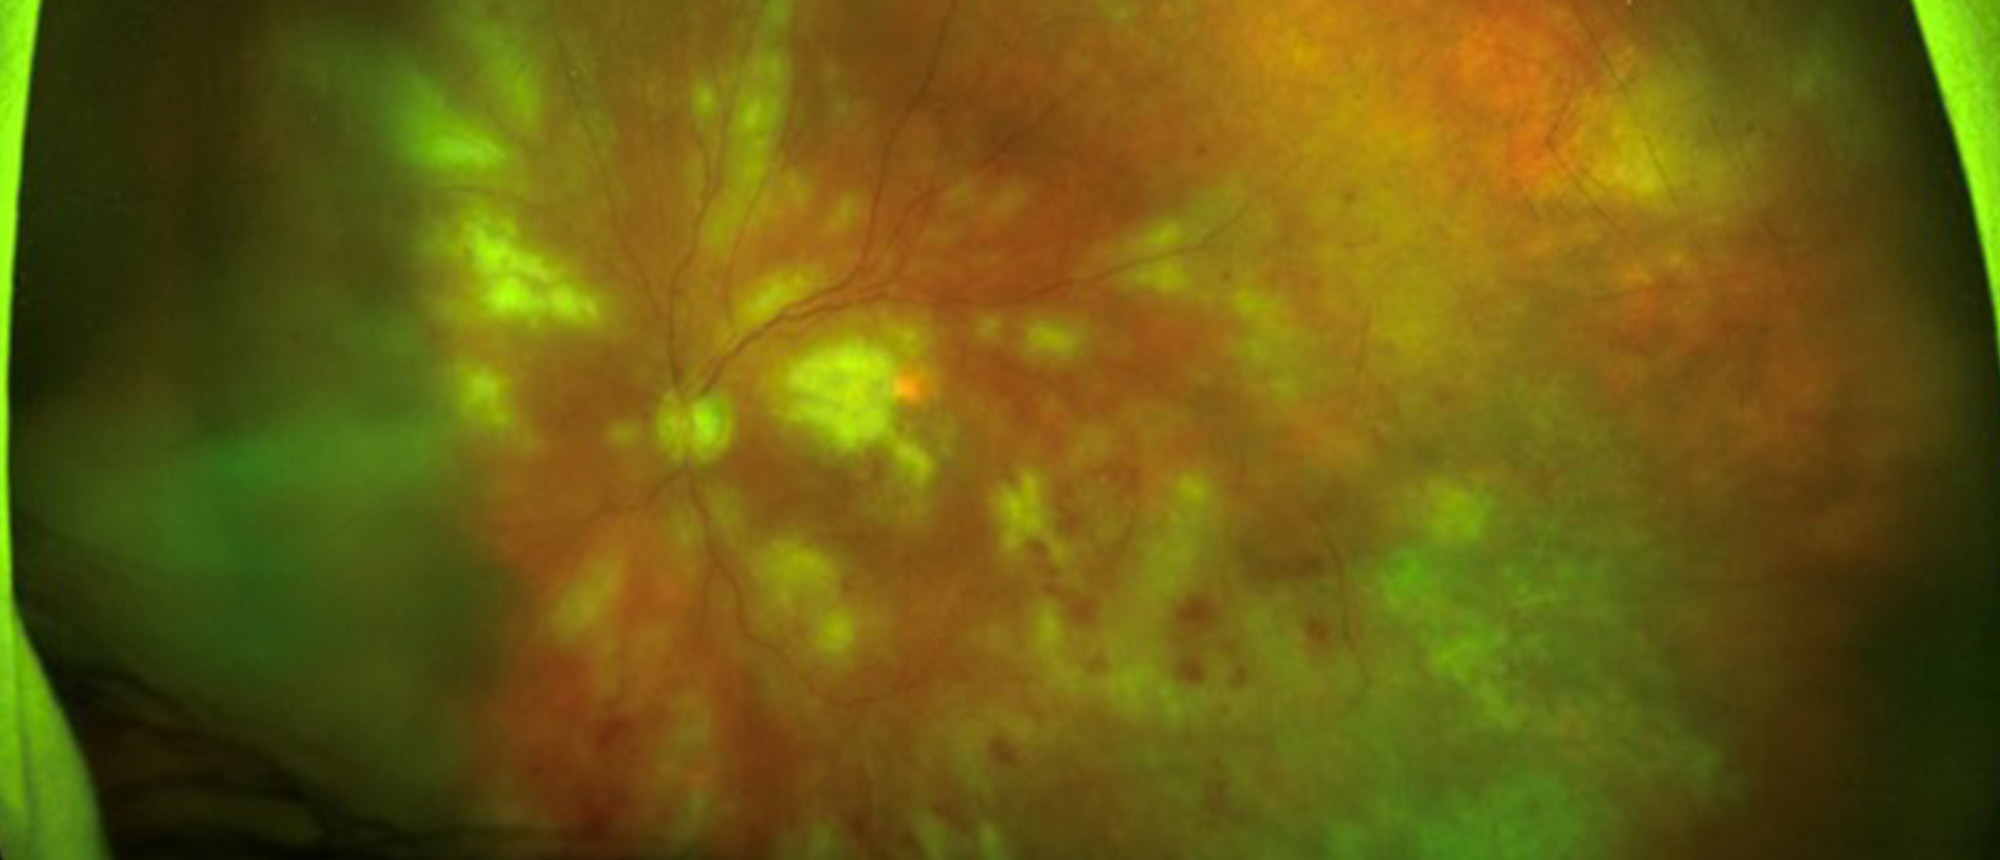

Acute Macular Neuroretinopathy A young patient presents with acute onset of blurry vision and scotoma. Visual acuity is 20/25 in both eyes. Exam reveals hypopigmented patches in the macula of both eyes, as well as a flame hemorrhage in the left. Imaging reveals disruption of the outer plexiform, ou…

Abstract A young patient presents with acute onset of blurry vision and scotoma. Visual acuity is 20/25 in both eyes. Exam reveals hypopigmented patches in the macula of both eyes, as well as a flame hemorrhage in the left. Imaging reveals disruption of the outer plexiform, outer nuclear, and photo…